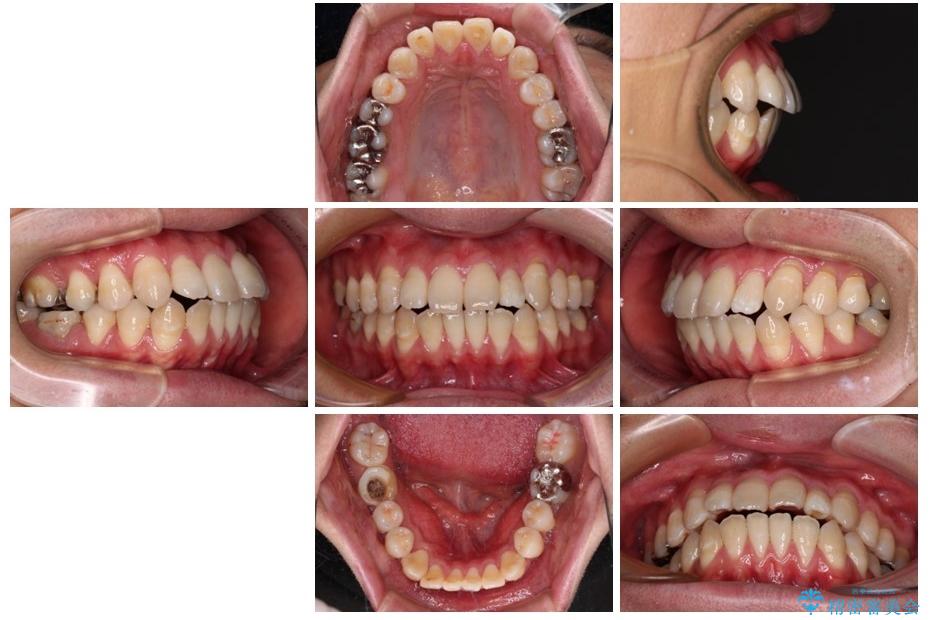

治療後

• 口元の突出感を改善!目立ちにくいワイヤー矯正で自信を持てる自然な横顔に 治療後画像

少しずつ前歯を後ろに下げていくことで、横顔のラインが整い、口元の“出っ張り感”が解消。

治療後には「自然に笑えるようになった」と嬉しいお声をいただきました。